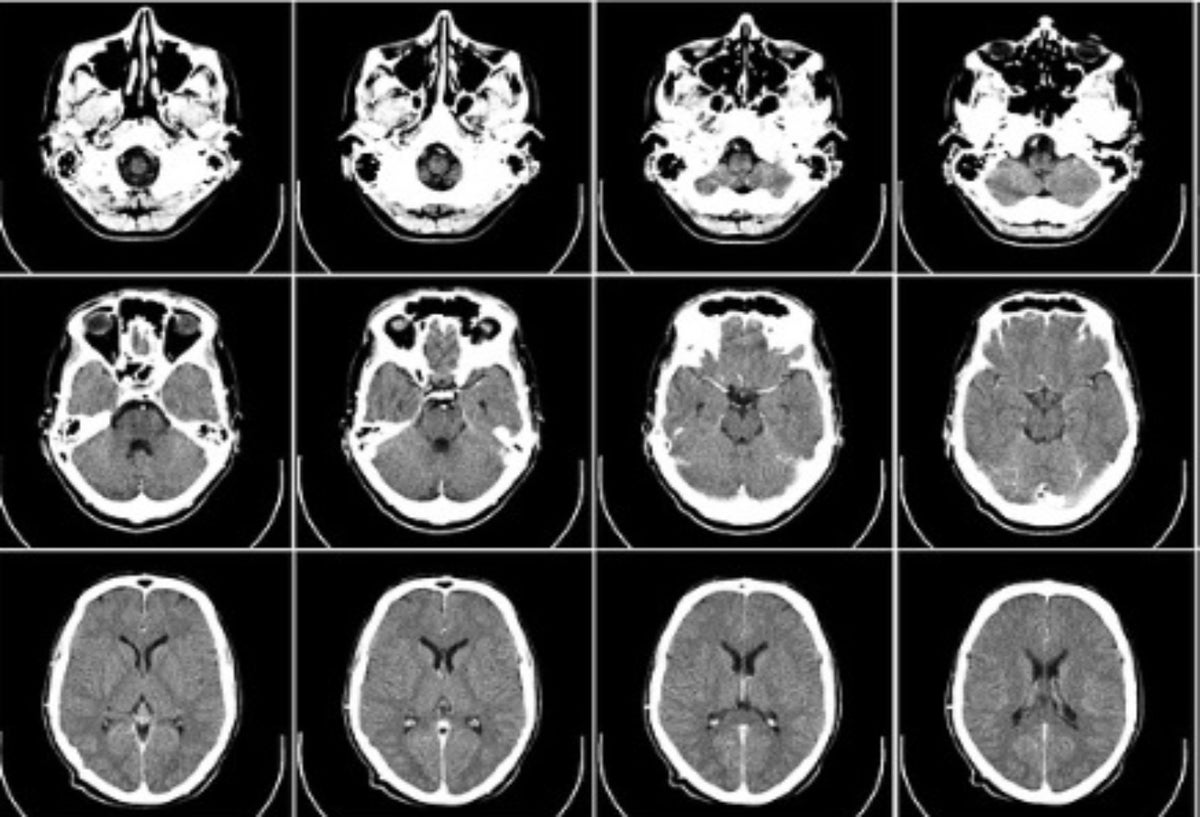

Crédito: Imagen Referencial de uso libre- Pixabay